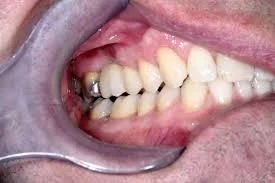

Fixed Retainers

These consist of a thin stainless-steel wire, which is permanently bonded behind the front teeth.

We usually fit your fixed retainers as soon as your braces are removed.

When you have this type of retainer you must try to be careful when brushing it and ensure you clean it thoroughly.

Like the other two types of retainers these serve the same purpose to help keep the teeth in the same position that they have been moved to.

An example of a fixed retainer before fitting